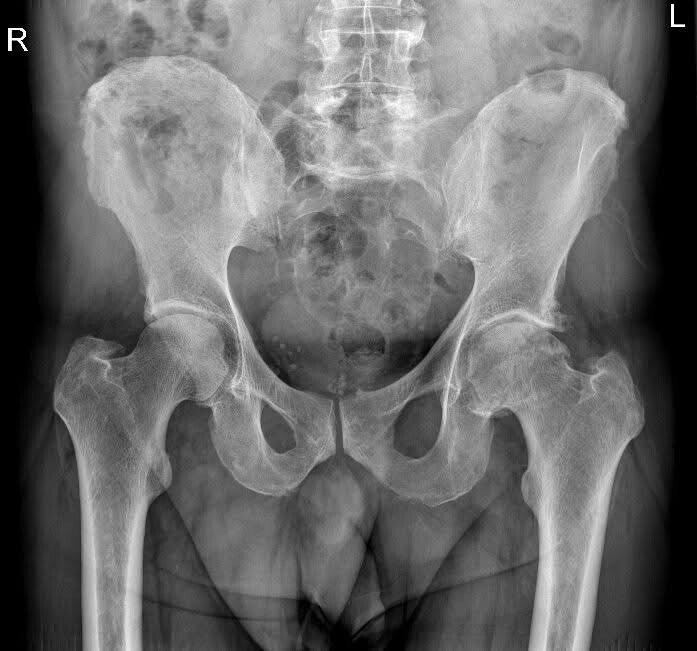

radiografia del bacino che mostra grave artosi di anca sinistra

La protesi d’anca sostituisce le superfici usurate dell’articolazione femoro-acetabolare con componenti artificiali in materiali avanzati (titanio, ceramica, polietilene ad alta resistenza).

Indicazioni

• Coxartrosi avanzata

• Necrosi della testa femorale

• Esiti di fratture

• Conflitto femoro-acetabolare evoluto

• Artriti infiammatorie